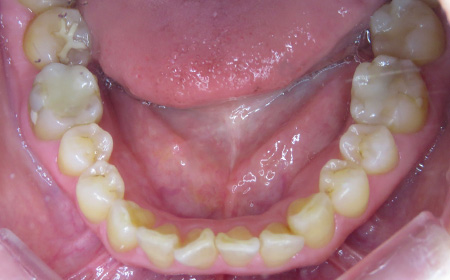

CASE01

Before

After